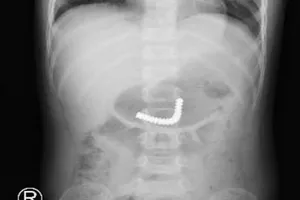

Giật mình khi đang ăn, người đàn ông bị mảnh xương cá diêu hồng cắm vào dây thanh quản 20/04/2022 13:53